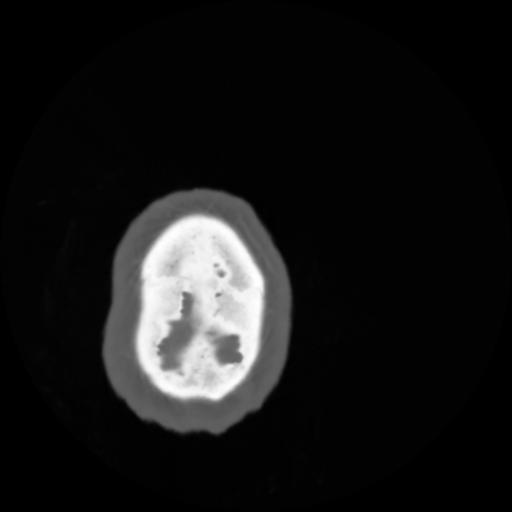

4 CEREBRO,,Vol,0.5,CEREBRO,,